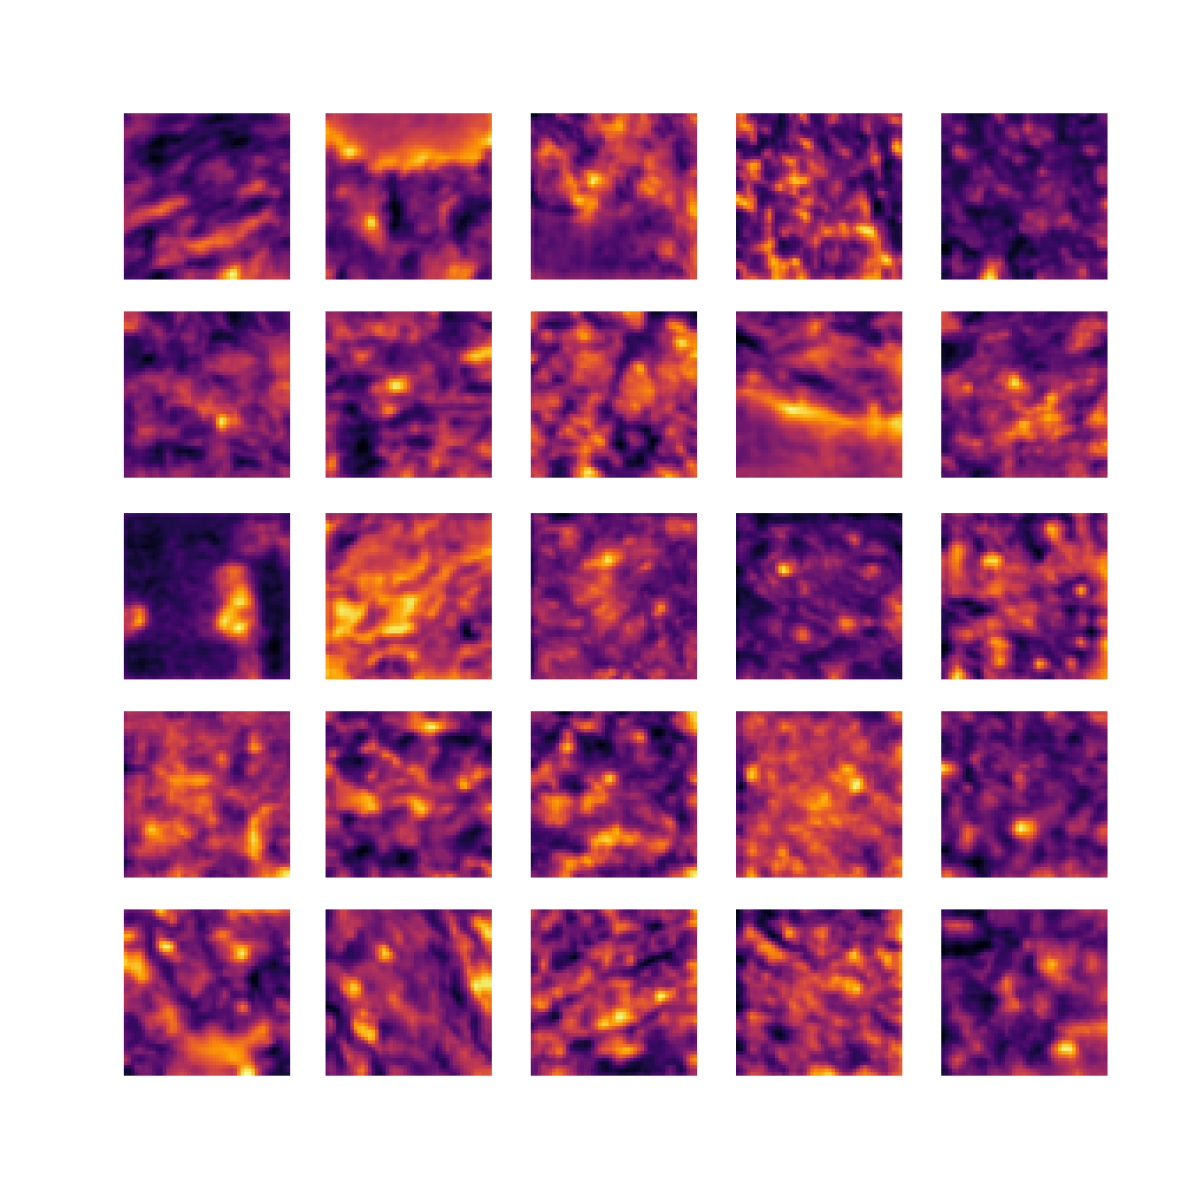

We also analyse the activation maps for each model using GradCAM as described in section S3. This offers more insight into the areas of the image which are contributing most heavily to the models’ representations. In Figure 4(b) we present some representative examples, however, a larger selection which was chosen at random is presented in Figures S10 to S25. The larger selection makes it easier to see the emergent patterns, including that privileged Siamese models tend to mainly identify features which are strongly present in both inputs, while unprivileged Siamese models tend to learn more diffuse features that are not specific to one cell phenotype or image region. TriDeNT ♆ incorporates both sets of features, learning both features specific to the privileged data and more the general features associated with unprivileged Siamese networks.

We can see in Figure 4(b) panel A that for ERG, the privileged Siamese model focuses almost exclusively on any nuclei which could be endothelial cells. As there are very few endothelial cells in the dataset, it could be an effective strategy to identify anything that could potentially be an endothelial cell to minimise the difference between the representations of the H&E model and the IF mask model. In the corresponding unprivileged Siamese image, we see that the model identifies some of these nuclei, albeit less strongly, but also focuses heavily on the other tissue and even the background, while strongly fixating on two spots of debris in the center of the image. This model has less ‘incentive’ to learn the weak features related to endothelial cells as these occur rarely and are not easy to detect, while more generic strong features such as the presence of connective tissue and the prevalence of background are more common and predictable from augmented images. We see that TriDeNT ♆ combines these two feature sets, strongly identifying nuclei while also identifying the connective tissue.

In panel C we see a similar pattern, with the privileged Siamese model fixating solely on the nuclei, while the TriDeNT ♆ model takes a more balanced approach. The unprivileged Siamese model appears to focus on a single cluster of nuclei while neglecting others, and similarly identifies an area of fibroblasts with its distinctive pattern but does not others.

In contrast to panels A and C which represent models with poor privileged Siamese results, panels B and D represent models whose privileged Siamese results were comparable to both TriDeNT ♆ and even the supervised baseline. It is therefore interesting to note that there are far more similarities between the privileged Siamese and TriDeNT ♆ models in both cases. Particularly in panel B, TriDeNT ♆ and the privileged Siamese model return virtually identical heatmaps, with both strongly identifying epithelial nuclei and neglecting the same areas of connective tissue. The unprivileged model in this case appears to focus solely on the centre of the image, giving a significantly different heatmap to the other panels.

Panel D again shows the previous pattern, with the privileged Siamese model identifying the features strongly present in the privileged data – fibroblasts – while neglecting the nuclei present. TriDeNT ♆ also strongly identifies the connective tissue, but, unlike the privileged Siamese model, does not completely neglect the nuclei. The unprivileged Siamese model primarily identifies background, and does not appear to identify the nuclei in this example.